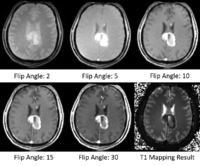

T1 mapping estimates effective tissue parameter maps (T1) from multi-spectral FLASH MRI scans with different flip angles. T1 mapping can be used to optimize parameters for a sequence, monitor diseased tissue, measure Ktrans in DCE-MRI and etc.

- Estimate effective T1 from multi-spectral FLASH MRI scans with different flip angles

- Test the Slicer module on MGH Brain Tumor MR Data with multiple flip angles